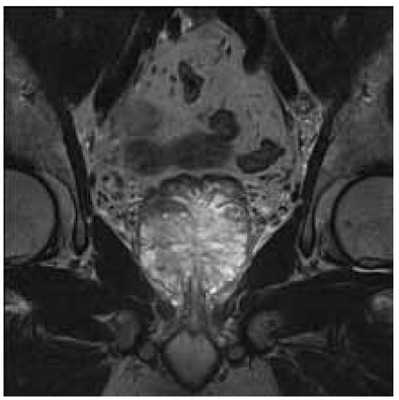

МРТ сегодня рассматривается как базовый метод диагностики РПЖ. На Т1 и Т2 взвешенных изображениях в предстательной железе очень хорошо видны опухолевые фокусы. Совершенно новые возможности дает метод диффузно взвешенных МРТ-изображений. Известно, что злокачественные клетки содержат очень мало воды и имеют низкий коэффициент диффузии. Поэтому они хорошо выделяются на фоне здоровых клеток, в которых содержится большое количество воды. Благодаря этому, диффузно-взвешенные изображения позволяют хорошо визуализировать злокачественных новообразований предстательной железы (рисунок 5).

Рисунок 5. Магнитно-резонансная томография на 3Т МР томографе с эндоректальной катушкой